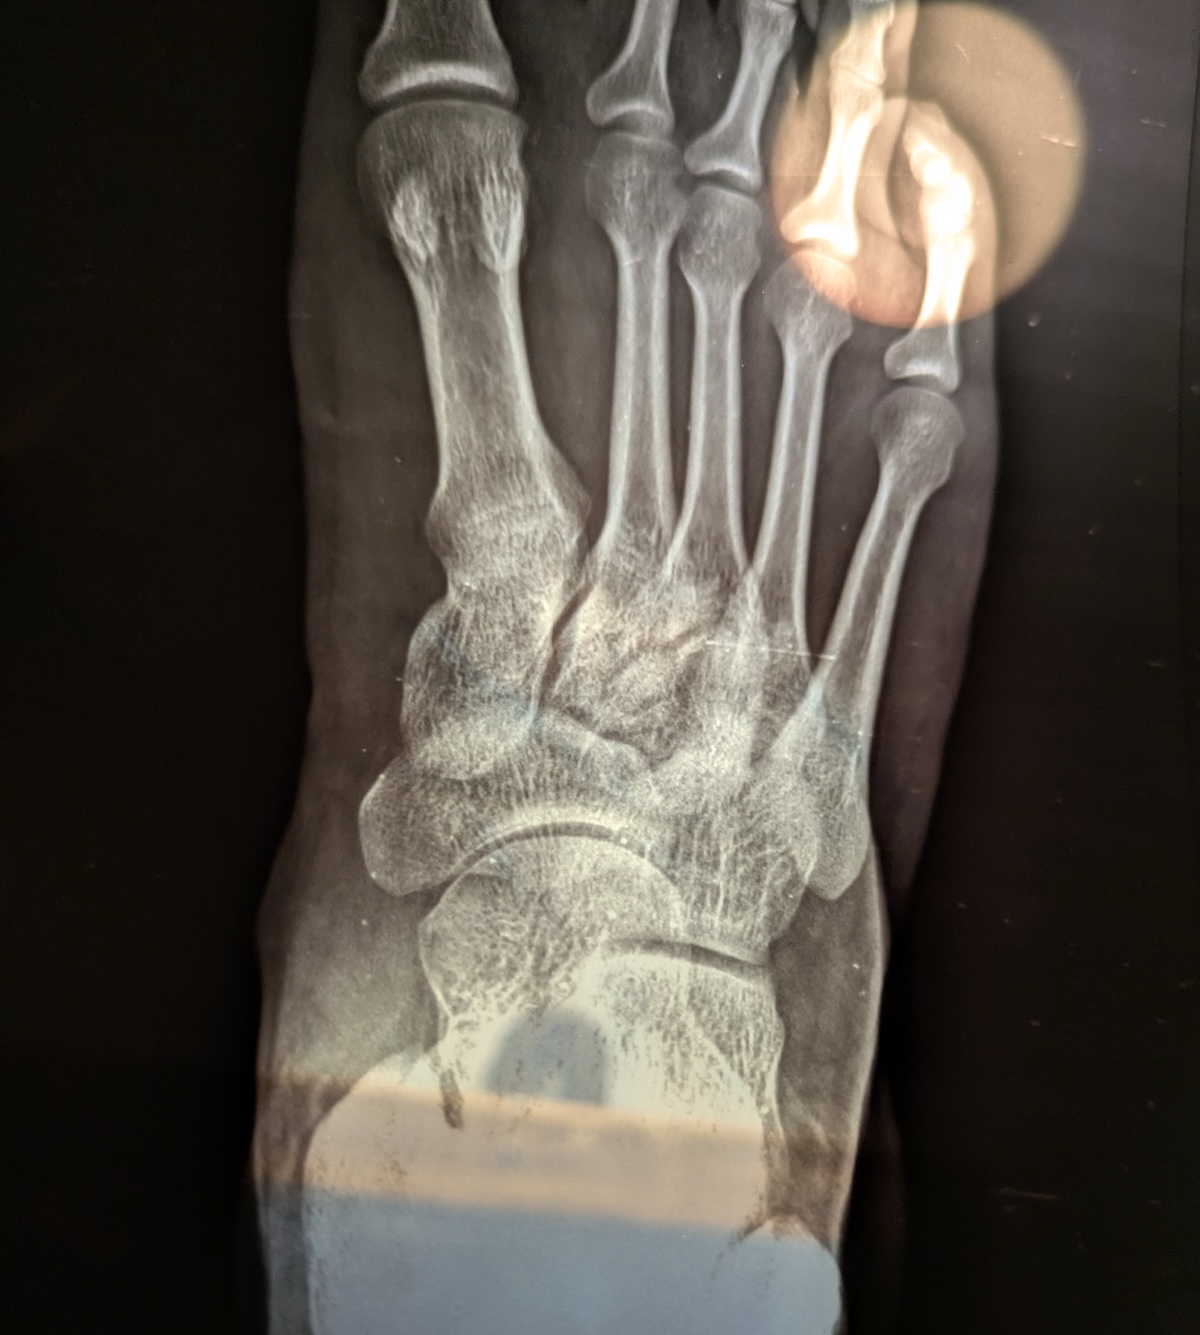

I stayed there for some time, and then somehow got myself home with the help of my friend. And the visit to the doctor revealed that there's a minor fracture between the end of second and third toes (you can probably see that in the x-ray report below) – it's like zig-zag.